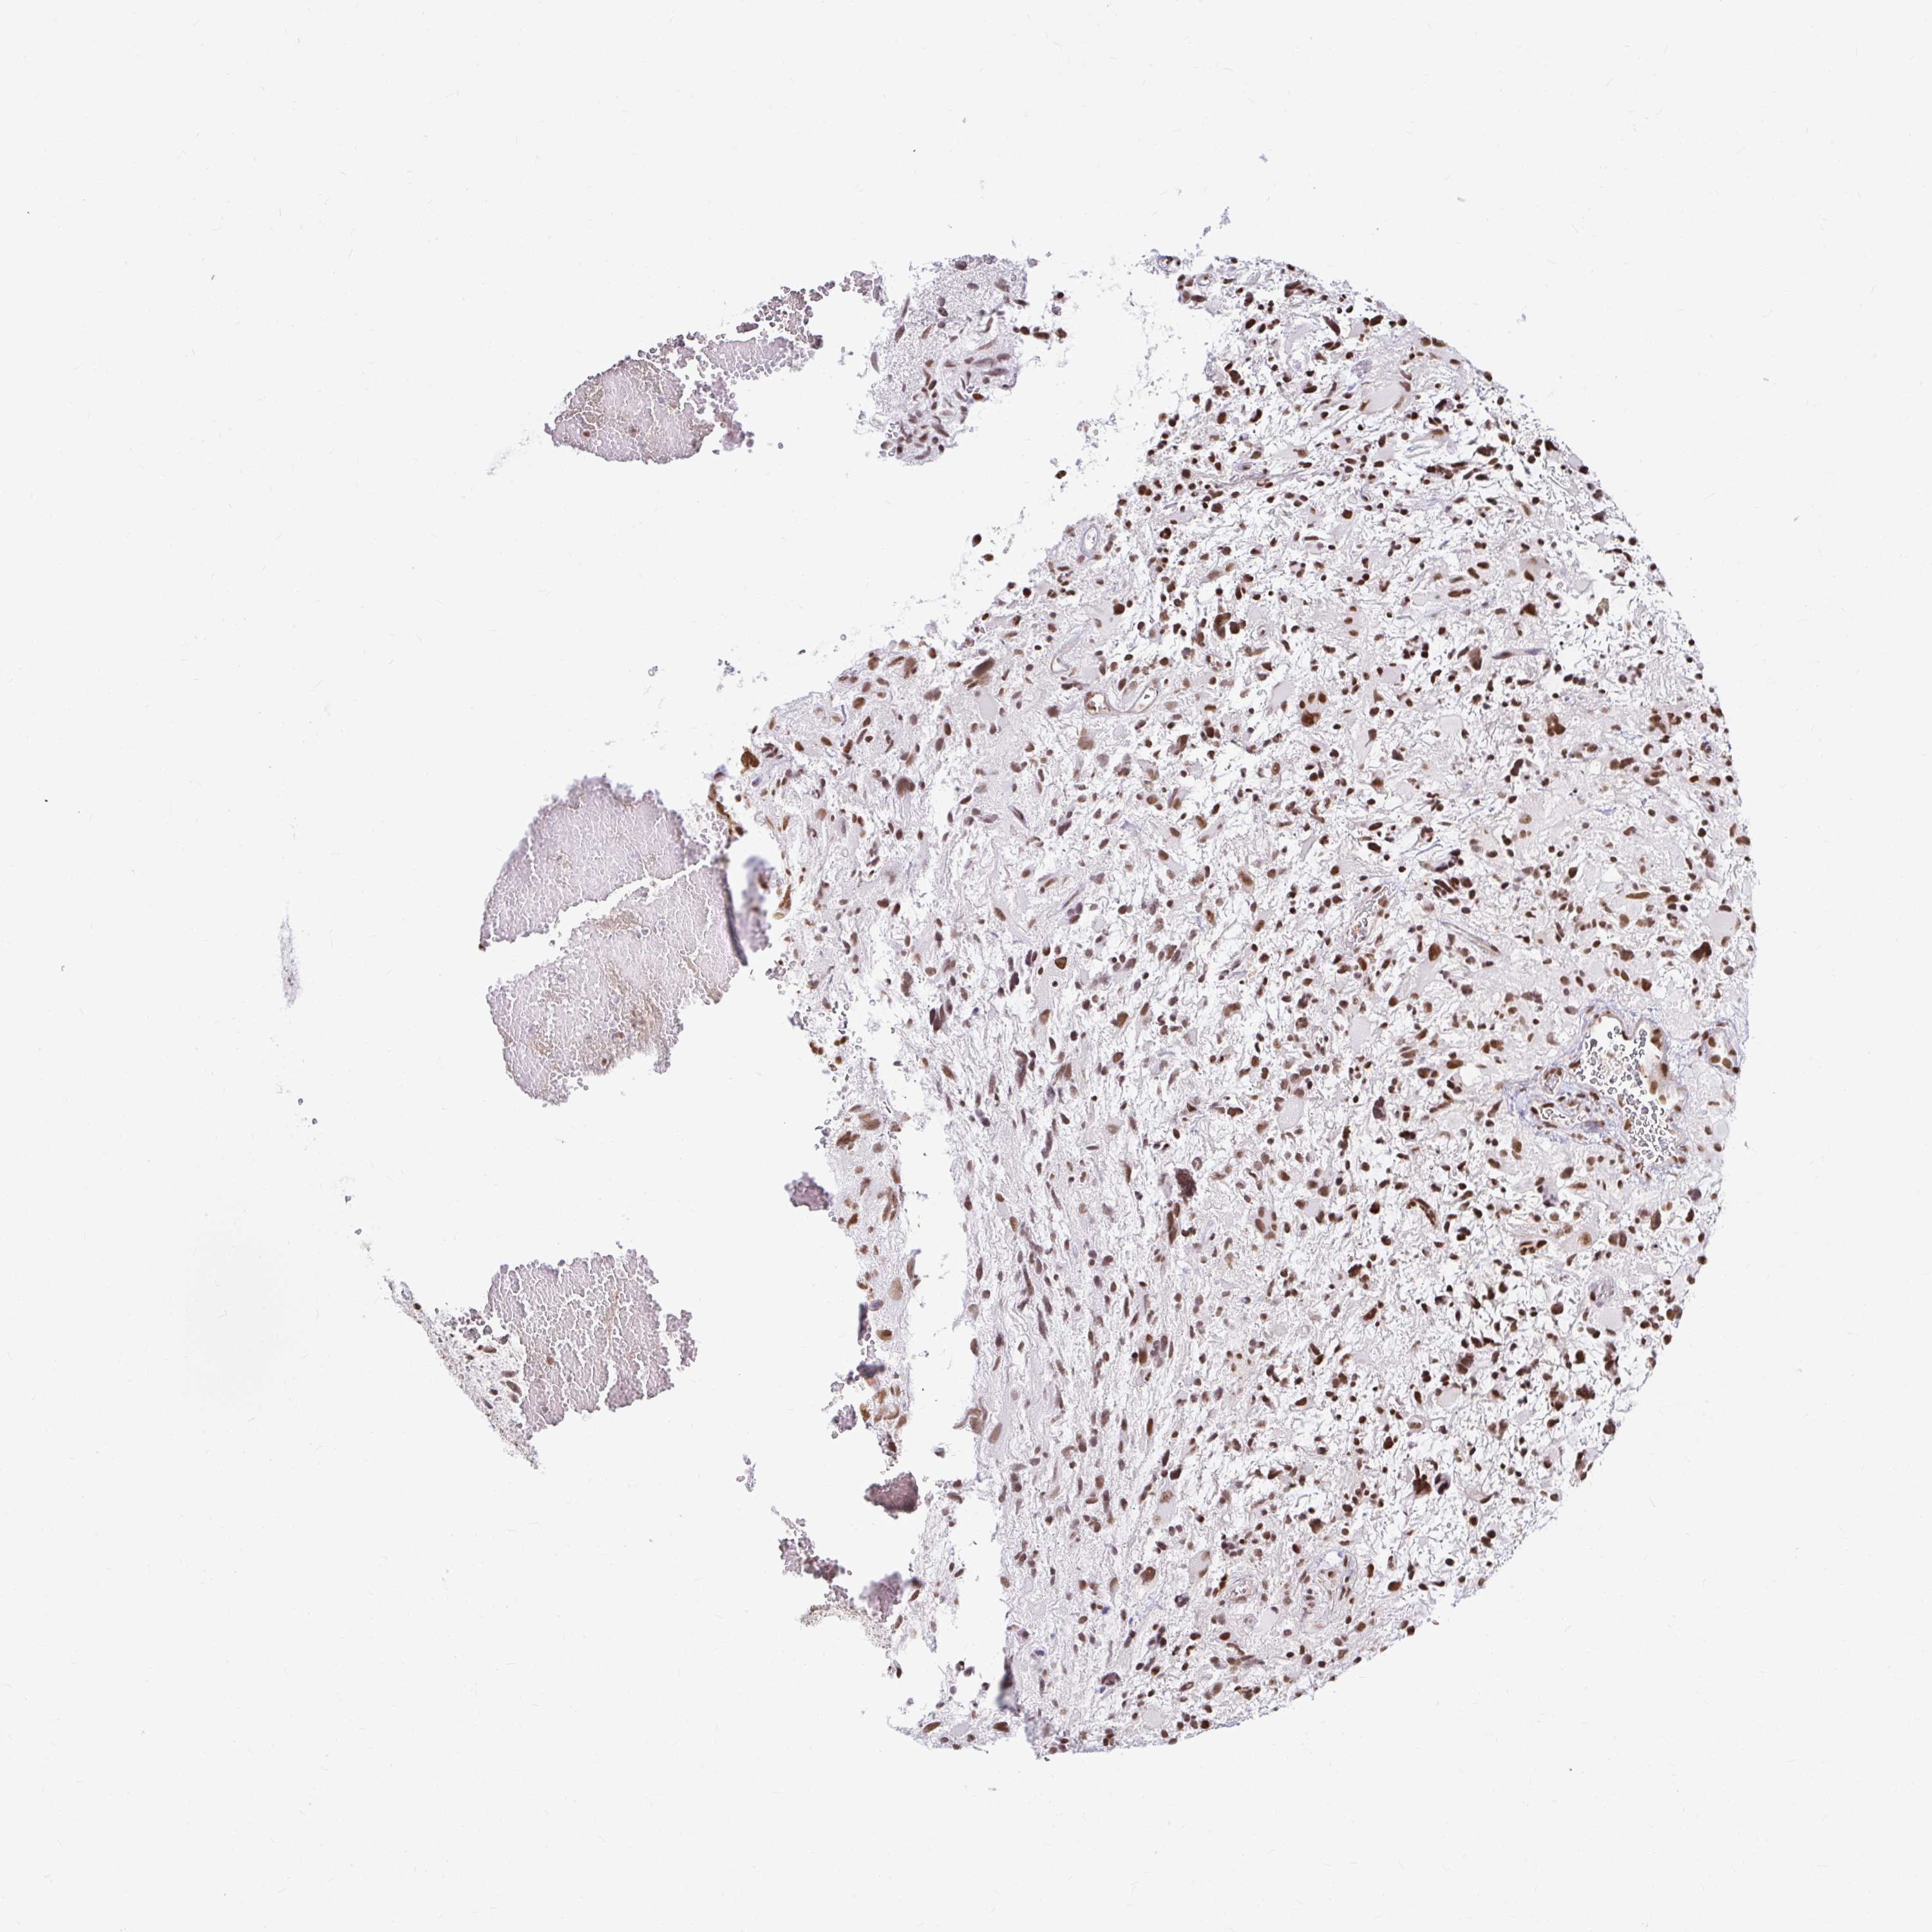

GLIOMA - Protein expressioni

A mouse-over function shows sample information and annotation data. Click on an image to view it in a full screen mode. Samples can be filtered based on level of antibody staining by selecting one or several of the following categories: high, medium, low and not detected. The assay and annotation is described here.

Note that samples used for immunohistochemistry by the Human Protein Atlas do not correspond to samples in the TCGA dataset.

Antibody stainingi

Antibody staining in the annotated cell types in the current human tissue is reported as not detected, low, medium, or high, based on conventional immunohistochemistry profiling in selected tissues. This score is based on the combination of the staining intensity and fraction of stained cells.

Each image is clickable and will lead to virtual microscopy that enables deeper exploration of all samples and also displays staining intensity scores, fraction scores and subcellular localization as well as patient and tissue information for each sample.

Antibody HPA041057

Antibody HPA058707

Antibody CAB011532

Staining

High

Medium

Low

Not detected

Intensity

Strong

Moderate

Weak

Negative

Quantity

>75%

75%-25%

<25%

None

Location

Nuclear

Cytoplasmic/membranous

Cytoplasmic/membranous,nuclear

Glioma, malignant, Low grade